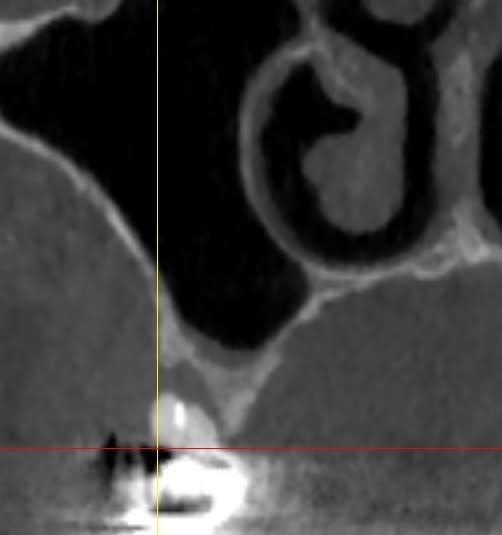

Et à priori on s.oriente également vers un soulevé de sinus.

Dans les cas où il reste 4 a 5mm d'os sous crestal, tu peux poser les implants en meme tps que le soulevé de sinus ( classification SA3 de Misch).